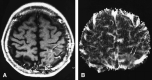

Background and purpose: Differentiation of tumor recurrence from treatment-related changes may be difficult with conventional MR imaging when newly enhancing lesions appear. Our aim was to determine the value of perfusion-sensitive contrast-enhanced MR imaging for differentiating recurrent neoplasm from nonneoplastic contrast-enhancing tissue.

Methods: Twenty patients in whom new enhancing lesions developed within irradiated regions were examined prospectively with perfusion-sensitive contrast-enhanced MR imaging. Twelve of them also underwent thallous chloride Tl 201 single-photon emission tomography (201Tl-SPECT). Normalized relative cerebral blood volume (rCBV) ratios and thallium indexes were evaluated to determine whether the new enhancing lesions were recurrent or not. Five instances of tumor recurrence and one of radiation necrosis were verified histologically; in the others, tumor recurrence was distinguished by lesions that progressively increased in size on serial MR examinations over at least 5 months, and nonneoplastic contrast-enhancing tissue was distinguished by lesions that disappeared or decreased in size on serial MR studies over at least 9 months.

Results: When normalized rCBV ratios were higher than 2.6 or lower than 0.6, enhancing lesions were either recurrent (n = 5) or nonneoplastic contrast-enhancing tissue (n = 3), respectively. All nonneoplastic contrast-enhancing tissue had a low thallium index, whereas three of four recurrent lesions had a high index.

Conclusion: An enhancing lesion with a normalized rCBV ratio higher than 2.6 or lower than 0.6 may suggest tumor recurrence or nonneoplastic contrast-enhancing tissue, respectively. In these cases, further examination with 201Tl-SPECT may not be necessary. However, when the normalized rCBV ratio is between 0.6 and 2.6, 201Tl-SPECT may be useful in making the differentiation.